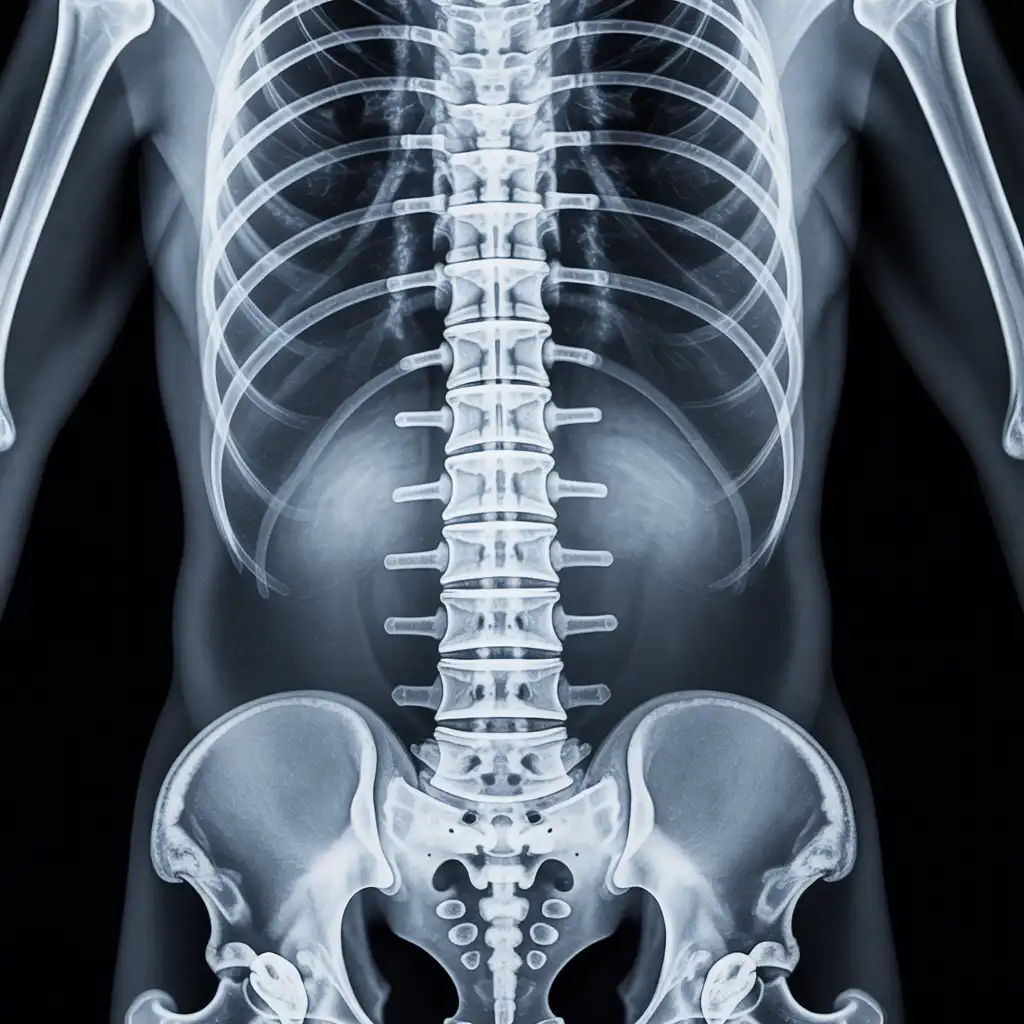

Una radiografia a domicilio è un esame radiologico eseguito da un tecnico specializzato che viene a casa tua con apparecchiature digitali portatili. L’esame si svolge sul posto, senza spostare il paziente e con la stessa qualità di una struttura ospedaliera.

Siamo un team di tecnici radiologi qualificati con anni di esperienza maturata in strutture sanitarie di Pescara e provincia. Abbiamo scelto di portare la diagnostica direttamente nelle case dei pazienti, offrendo radiografie a domicilio con la stessa precisione degli esami eseguiti in ambulatorio, ma con tutta la comodità del proprio ambiente. Nel tempo abbiamo eseguito migliaia di esami a domicilio in abitazioni private, residenze per anziani e centri assistenziali, utilizzando apparecchiature digitali portatili certificate e procedure rapide, sicure e adatte anche ai pazienti con difficoltà di movimento. Con Radidom Pescara mettiamo al centro la persona: competenza, cura e tecnologia al servizio della tua salute, ovunque tu sia.